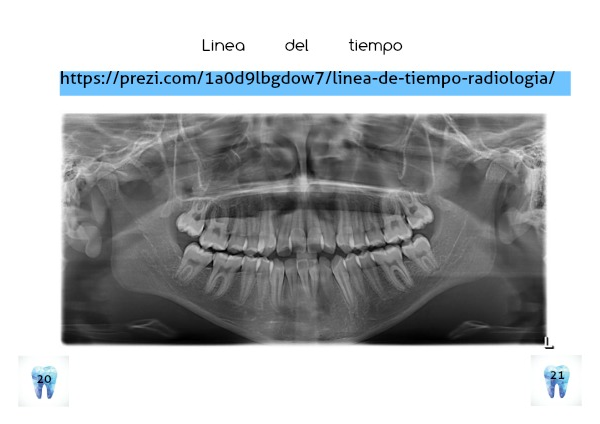

Linea del tiempo

https://prezi.com/1a0d9lbgdow7/linea-de-tiempo-radiologia/